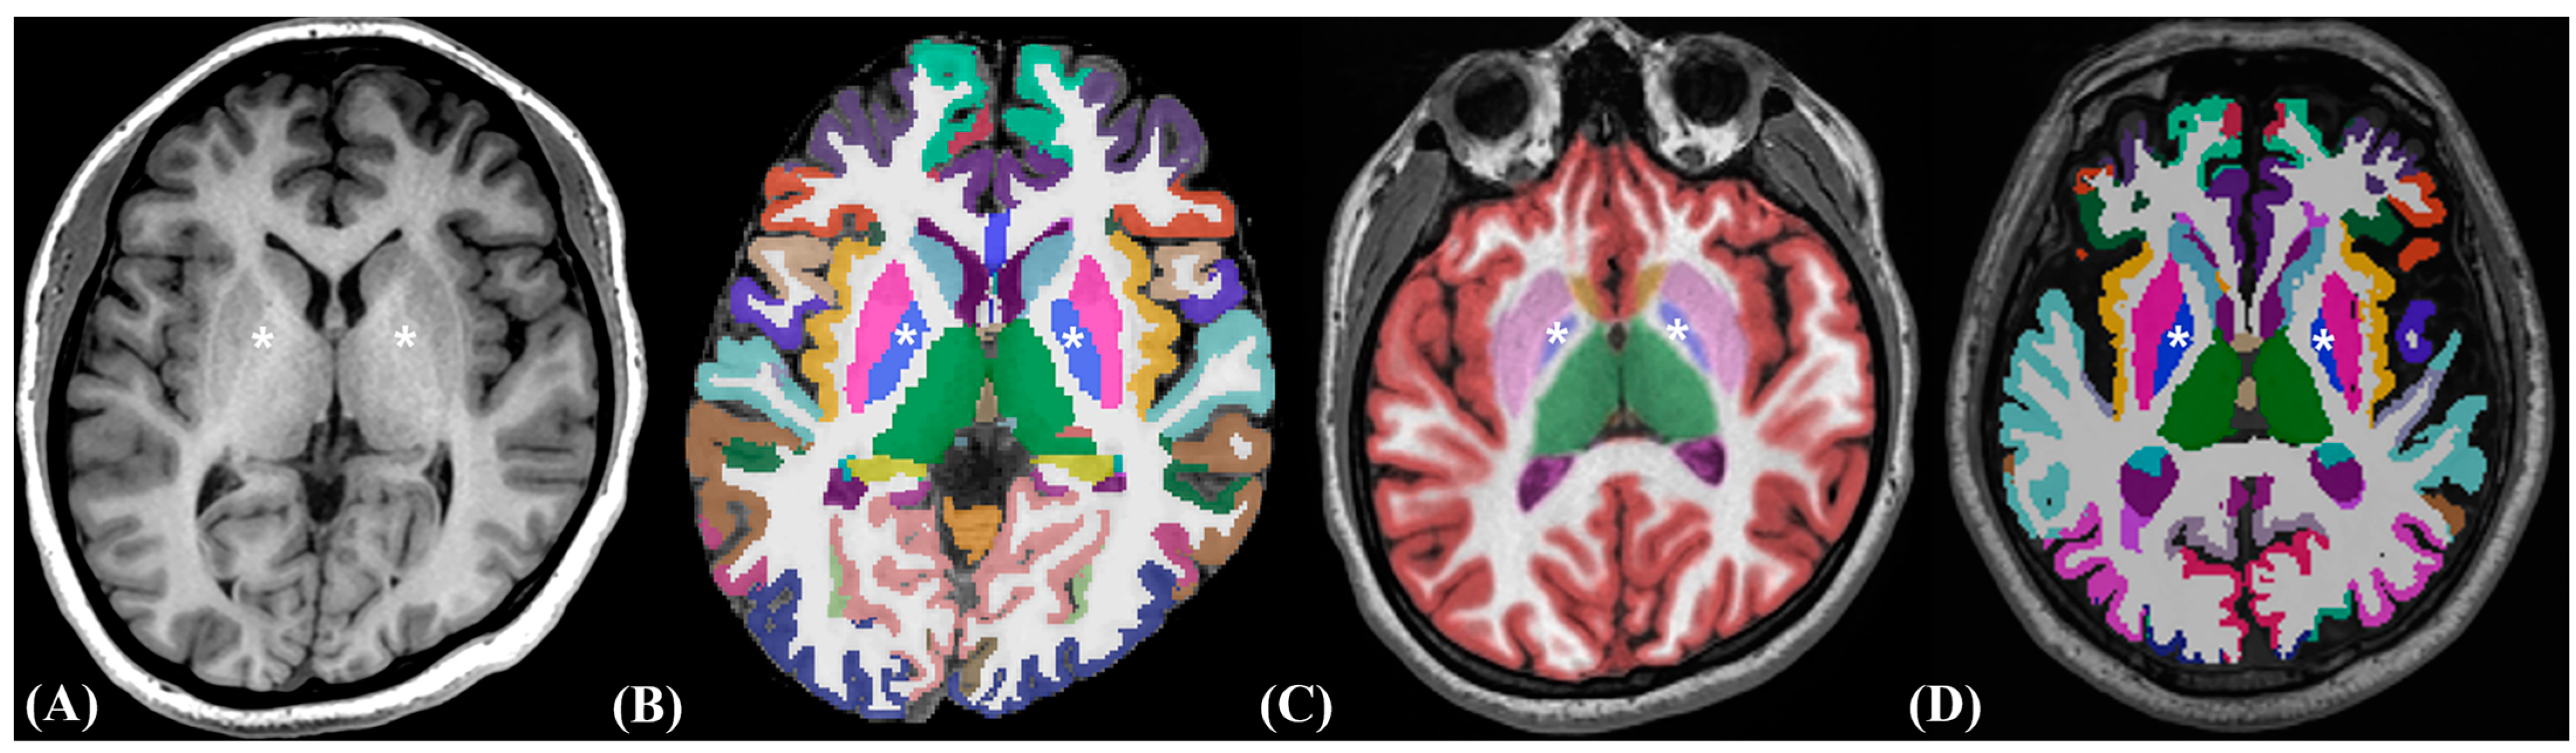

2.3. Image Post-Processing Volumetric Procedures